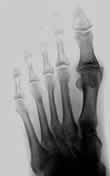

Hallux rigidus (Großzehengrundgelenksteifigkeit)

Durch Abnutzung des Großzehengrundgelenkes kommt es zu zu zunehmenden belastungsabhängigen Schmerzen. Im weiteren Verlauf tritt eine Einschränkung der Beweglichkeit auf. Schließlich sind der Gelenkknorpel oder auch das ganze Gelenk zerstört und die Großzehe ist steif.